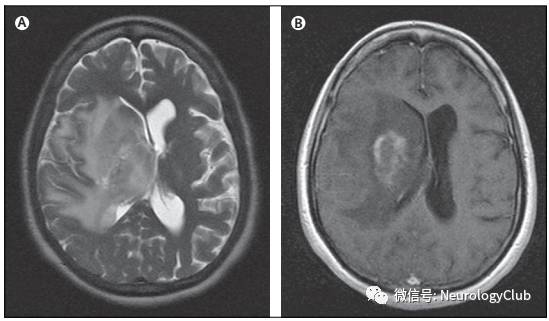

神经白塞病包括实质型和非实质型。实质型神经白塞病约占70-80%,病灶以脑干(脑桥、中脑)常见,也可延伸累及间脑、基底节区。累及大脑半球时,常为多发的小白质病变,也可表现为孤立性类瘤样病灶。脊髓受累时可见单发或多发的不同长度的炎性病变,常位于颈胸髓。也可有脑膜脑炎,表现为脑膜强化。急性期病灶在T1WI上呈等-低信号,增强通常为片状强化,也可出现环形强化,T2WI和FLAIR上为高信号,DWI上高信号,相应ADC值降低。部分病灶中心或周围可见出血。累及脊髓时横断面T2WI可见“百吉饼(在美国纽约较为流行,也称硬面包圈)征(Bagel Sign)”。慢性期,病灶多缩小,通常无强化,可见脑萎缩,尤其是脑干。

(图9:A:左侧内囊丘脑区假瘤样较大病灶;B:治疗后明显改善)